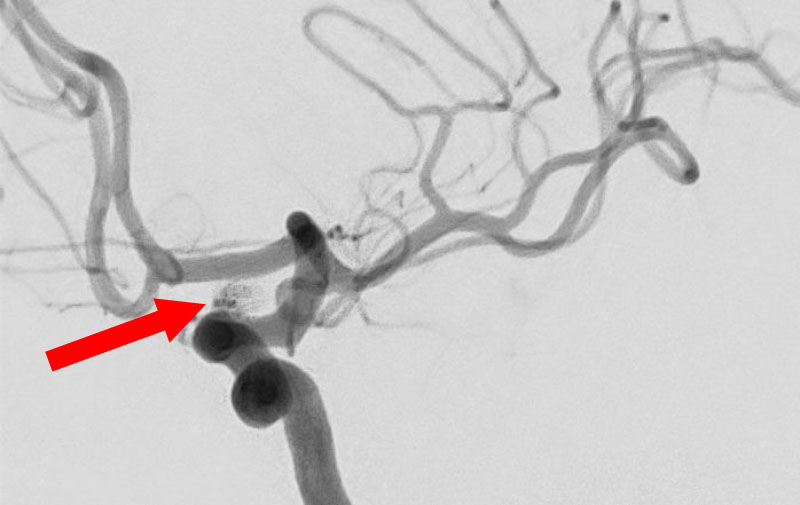

くも膜下出血

左中大脳動脈瘤破裂

40代

救急外来

No.1596 手術前

No.1596 手術中

No.1596 手術後